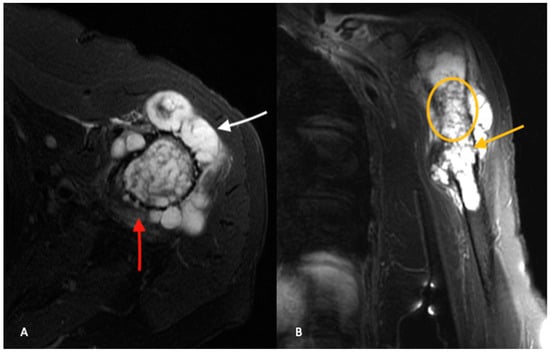

High-grade tumors usually present as larger lesions with less mineralization, with a moth-eaten appearance and permeative bone destruction (Figure 2A,B) [15]. Higher-grade lesions can cause more extensive endosteal scalloping that can result in cortical destruction or pathologic fracture. Soft tissue masses are seen in approximately 50% of cases. However, despite these characteristic differences, plain radiographs are not reliable in determining tumor grade [15].

When compared to ACTs, high-grade chondrosarcomas have a higher prevalence of loss of entrapped fatty marrow, cortical breakthrough and extraosseous soft tissue masses (Figure 3A,B) [18]. These findings are neither pathognomonic nor universally present and MRI findings must be considered in the setting of clinical and histologic findings when differentiating between ACTs and high-grade chondrosarcomas.

Figure 2. AP (A) and lateral (B) radiographs demonstrate an aggressive, heterogenous lytic lesion in the left proximal humerus with a wide zone of transition (white arrows). The lesion measures greater than 5 cm in length. Chondroid matrix is demonstrated. Periosteal reaction is present at the lateral aspect. There is a large area of cortical breakthrough at the anterior cortex, in addition to numerous areas of endosteal scalloping. Computed tomography (C) further demonstrates the cortical disruption and chondroid matrix formation (white arrow).

Figure 3. Axial (A) and coronal (B) T2-weighted, fat-saturated MR images of the same patient in Figure 2 confirm present of a chondroid lesion (yellow circle) with aggressive features, including cortical breakthrough (white arrow) and numerous areas of endosteal scalloping (yellow arrow). There is a significant amount of extra-osseous chondroid tumor. Perilesional edema (red arrow) is seen extending into the adjacent soft tissues.